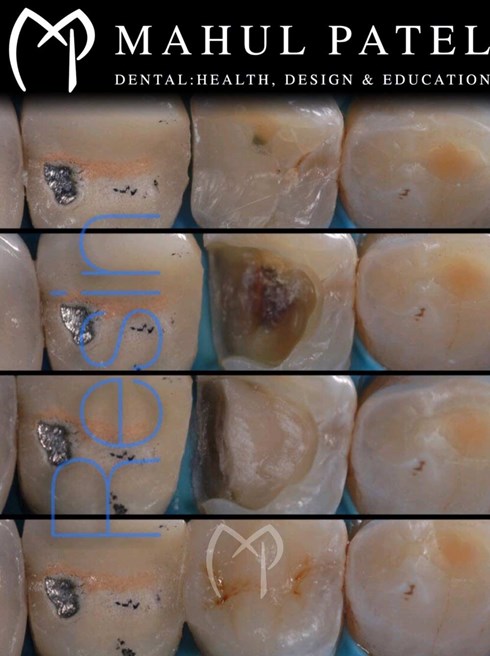

• Fillings

• Bonding and restoration build-up of teeth